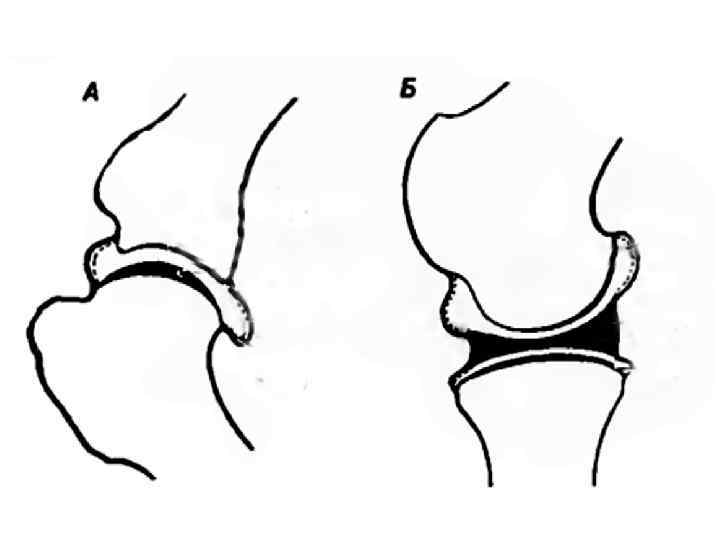

ВОПРОС № 27. Ложный сустав и его причины Ложный сустав — вариант процесса сращения костных отломков, когда по прошествии двойного среднего срока, необходимого для формирования полноценной костной мозоли, рентгенологические признаки консолидации отсутствуют

Псевдоартроз (др. название «неоартро з» ) — это ложный сустав, образовавшийся на несвойственном ему месте вследствие длительно существующего вывиха или внутрисуставного перелома. Врожденный вывих бедра может стать причиной возникновения псевдоартроза.

ВТОРИЧНЫЕ БОЛЕЗНЕЙ СУСТАВОВ ОБУСЛОВЛЕННЫЕ ПЕРВИЧНЫМ ПОРАЖЕНИЕМ КОСТЕЙ Болезнь Легга-Пертеса у собак (некроз головки бедренной кости) СЧИТАЕТСЯ, ЧТО РАЗРУШЕНИЕ СУСТАВА ПРОИСХОДИТ ВСЛЕДСТВИИ ИШЕМИИ КСТНОЙ ТКАНИ ШЕЙКИ И ГОЛОВКИ БЕДРА